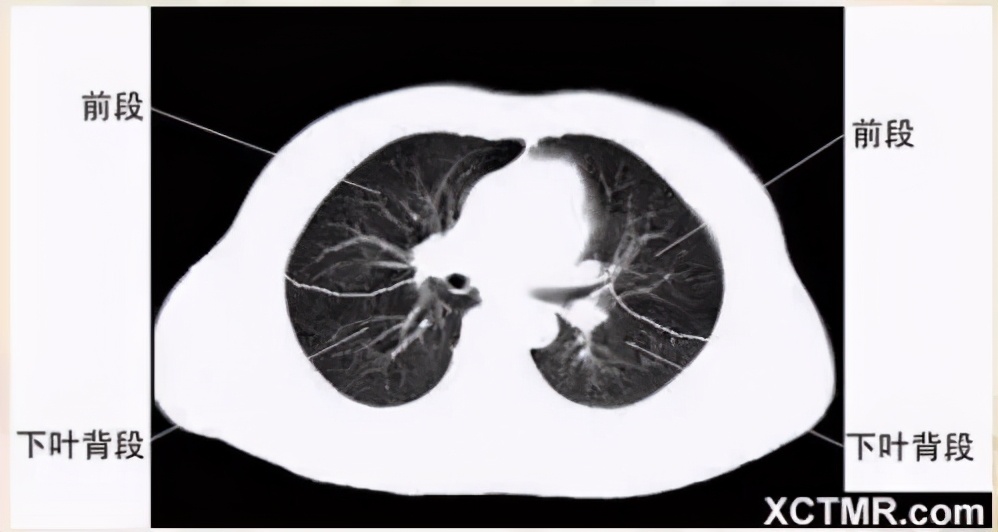

肺段划分